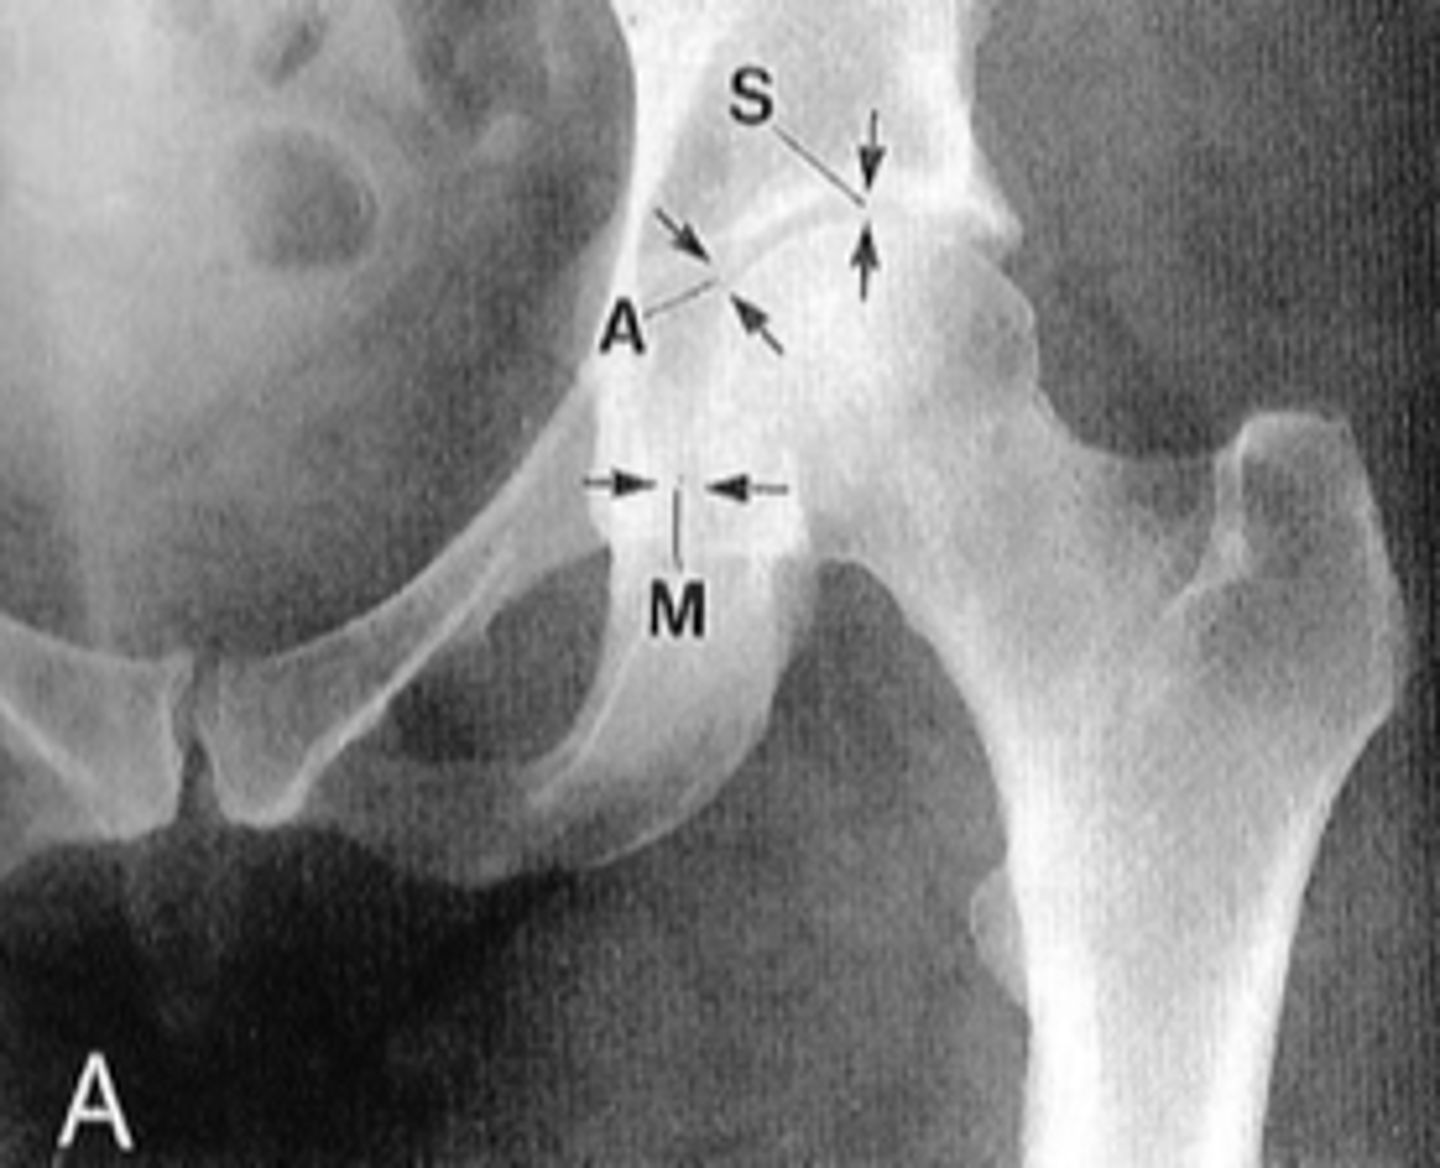

Shenton's line

ID measurement

<p>ID measurement</p>

- AP hip

- AP pelvis

What views are used to see Shenton's line?

<p>What views are used to see Shenton's line?</p>

- Smooth arc along femoral neck

- Obturator foramen

Shenton's line landmarks

<p>Shenton's line landmarks</p>

Continuous and smooth

Shenton's line normal measurements

<p>Shenton's line normal measurements</p>

62

- Hip dislocation

- Femoral neck fracture

- Slipped epiphysis

Clinical significance of Shenton's line

<p>Clinical significance of Shenton's line</p>